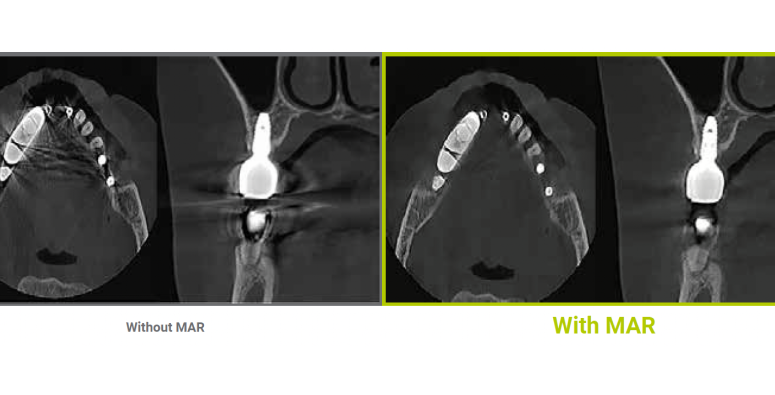

Game-changing Dentium MAR (Metal Artifact Reduction) with live comparison automatically reduces metal artifacts caused by implants, fillings or restoration. This helps to confirm diagnosis and reduces the risk of misinterpretation.